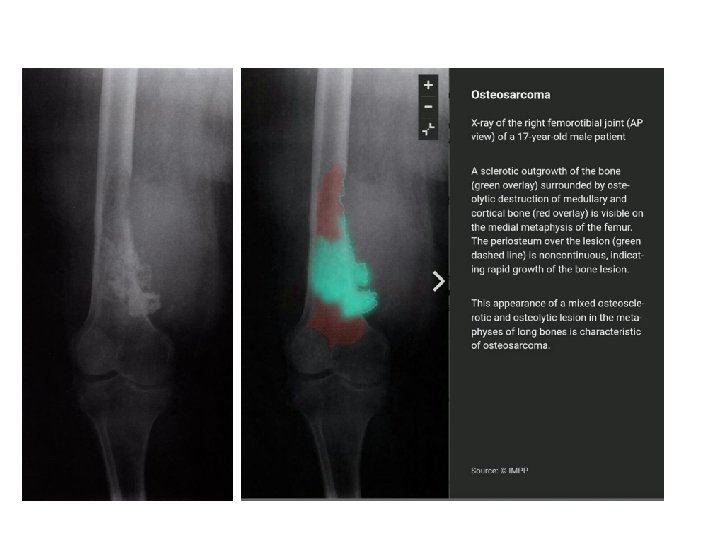

Osteosarcoma Primary osteosarcoma: unknown Secondary osteosarcoma: Paget's disease of bone, radiation injury, bone infarction Incidence: bimodal distribution Primary osteosarcoma: puberty/adolescence Secondary osteosarcoma: advanced age Sex: ♂ > ♀

The sites most commonly involved are the metaphyseal region of long tubular bones, especially the region around knee joint 50% Pain is usually the first symptom; it is constant, worse at night and gradually increases in severity. Sometimes the patient presents with a lump. Pathological fracture is rare. Metastases